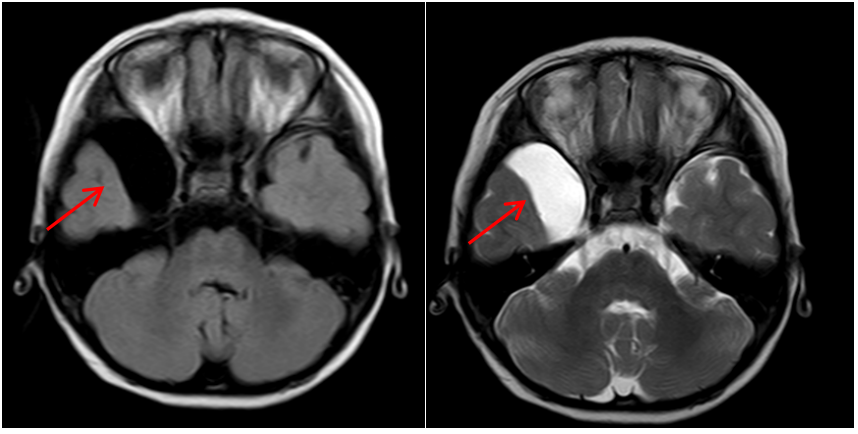

1.小骨窗显微手术:是治疗儿童脑型肺吸虫病的有效方法,具有缩短手术时间,显微镜下顺利寻找病灶边界,减少对周围正常脑组织的牵拉。手术创伤小、恢复周期短,做到对脑组织及周围神经损伤最小。

4. 蛛网膜囊肿